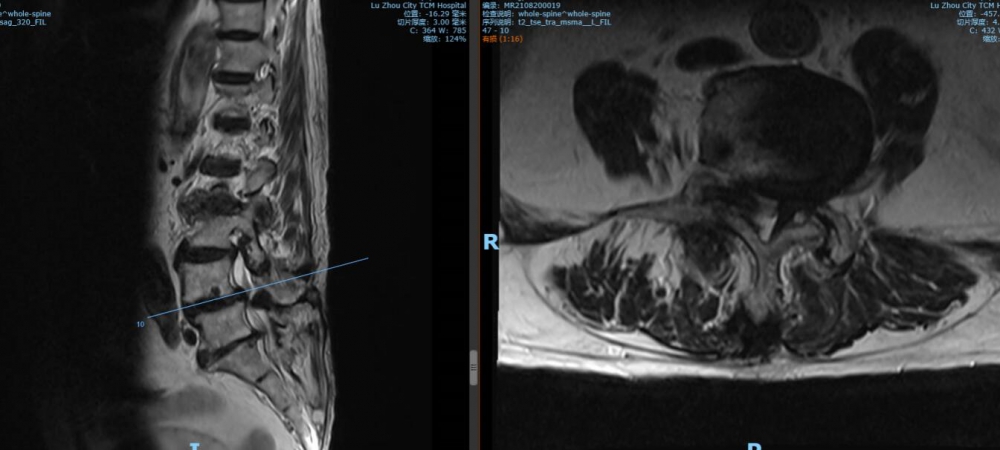

腰4 5椎間盤MRI

腰5 骶1椎間盤MRI

瀘州市中醫(yī)醫(yī)院骨傷二科主治中醫(yī)師胡建超介紹,李謹行老人患有腰椎管狹窄癥 、腰4椎I°滑脫 、脊柱退行性側(cè)彎畸形 、冠狀動脈粥樣硬化性心臟病、心律失常、高血壓2級等17種疾病,同時處于慢性阻塞性肺病加重期和腦梗塞恢復期。92歲、全身多種疾病,隨時可能會有突發(fā)情況,要做這樣一個大手術(shù),對醫(yī)生和患者來說,無疑都是一個巨大的挑戰(zhàn)。